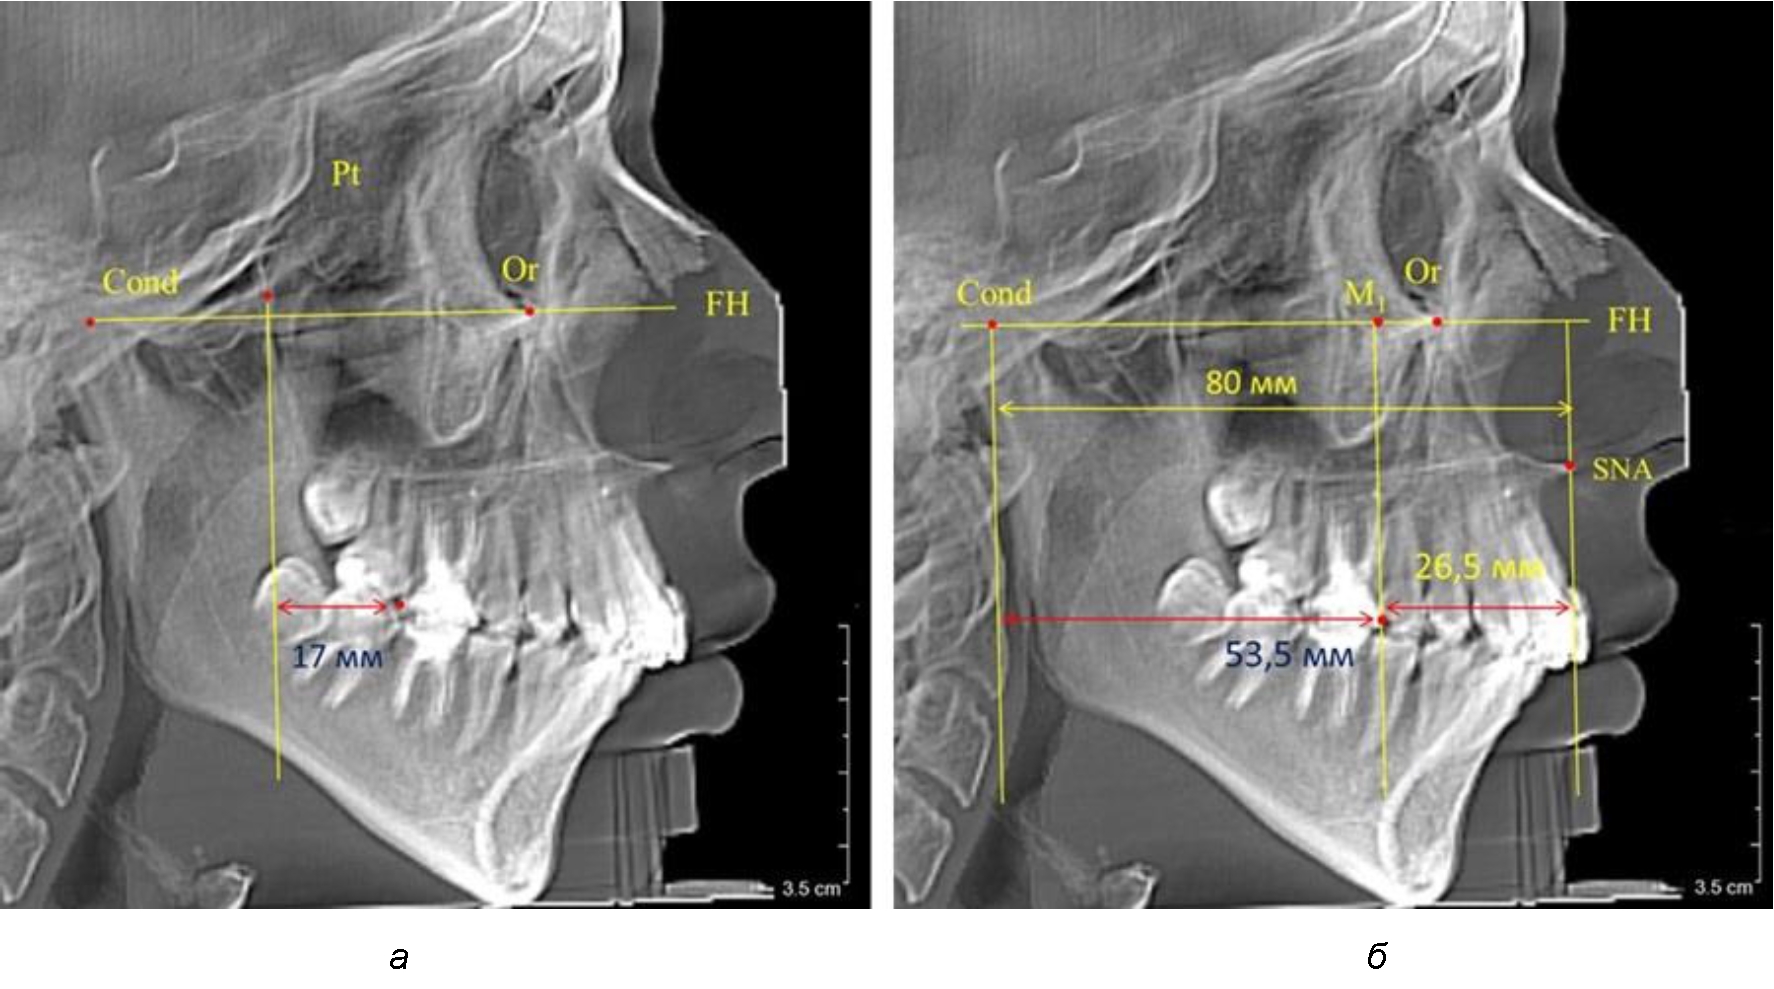

При проведении анализа к Франкфуртской горизонтали проводили передний и задний перпендикуляры. Передний спинальный перпендикуляр проходил через выступающую точку передней носовой ости (spina nasalis anterior – SNA), а задний суставной перпендикуляр опускали из кондилярной точки Cond. Молярный перпендикуляр проводили через медиальную поверхность первого постоянного моляра. Указанная вертикаль отделяла замещающие зубы постоянного прикуса от добавочных зубов (постоянных моляров), что вполне логично для анализа положения первых постоянных моляров в гнатическом комплексе (рис. 1).

Рис. 1. Метод определения положения первых верхних моляров по Ralph E. McDonald (а) и по предложенному методу (б)